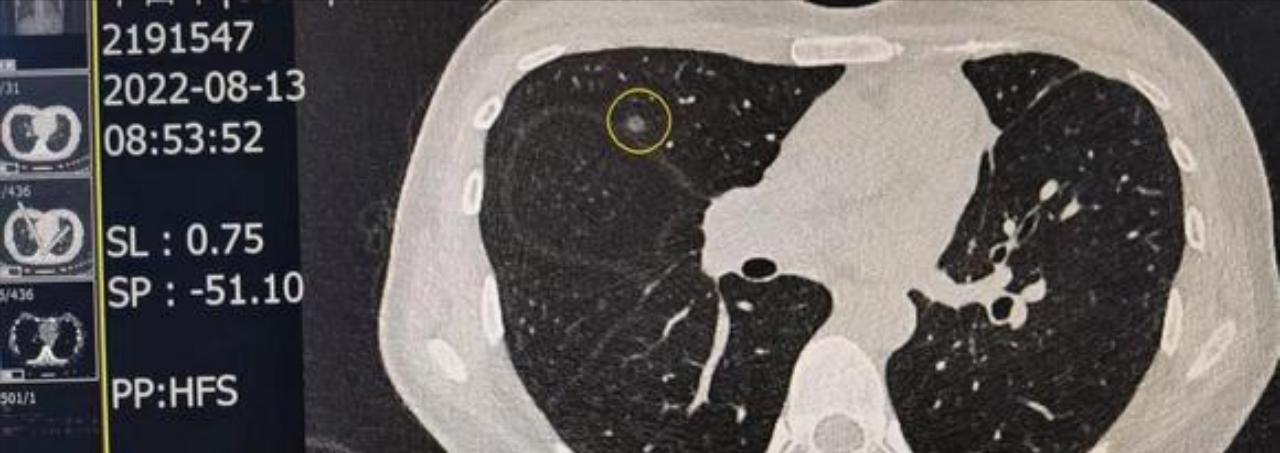

请戴主任解惑,我今年39岁,不抽烟,无高危粉尘环境,无不良嗜好;2021年10月体检发现双肺有3个磨玻璃结节,分别于2022年1月和9月在本地医院手术切除。术后病理结果为1个原位癌1个微侵润1个侵润,侵润的位置在右肺下叶,贴壁状生长为主的腺瘤,肿瘤大小1厘米*0.4厘米, 侵犯脏层胸膜,未见转移。基因检测19del突变。

术前CT(2022/8/13)